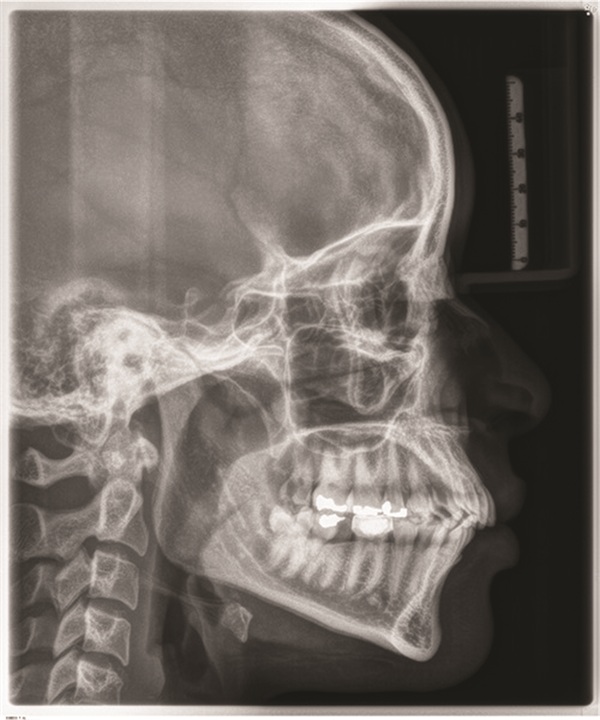

Records showed oversized maxillary incisors, canines, and premolars, with a Bolton discrepancy of 13.4 mm excess in the upper anterior segment and 9.5 mm overall (Figs. 1–6). The original poster anticipated needing digital setup models and suspected upper premolar extractions might be required. The central question posed to the forum was straightforward: How should this case be treated?

Beyond tooth-size discrepancy and mechanics, contributors advised evaluating condylar morphology and screening for temporomandibular symptoms before initiating treatment. The panoramic image suggested asymmetry, though the original poster clarified that the radiograph appeared distorted and the patient was asymptomatic.